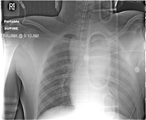

Laparoscopic cholecystectomy for gallstone pancreatitis in a patient with situs inversus totalis

Angela E.E. Fanshawe and Kamran Qurashi

Journal of Surgical Case Reports, Volume 2017, Issue 2, February 2017, rjx003, https://doi.org/10.1093/jscr/rjx003